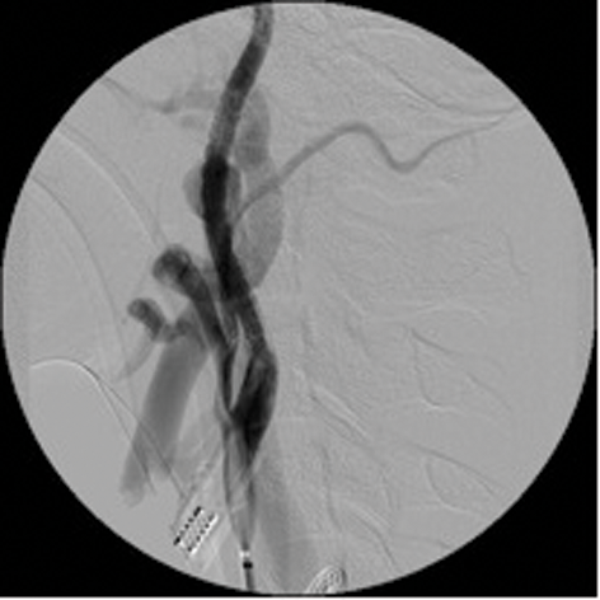

Embolisation is very effective in minimising intraoperative blood loss and is now a well-accepted part of the treatment of JNA [2]. (Figure 1 shows a case of preoperative embolisation of a juvenile angiofibroma).

Figure 1: Juvenile angiofibroma before and after embolisation.